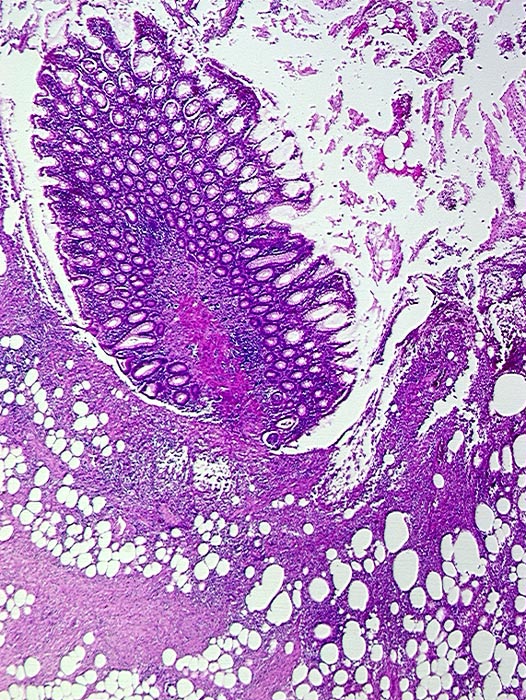

Divertikulitis

Makroskopie

Pathologischer Befund